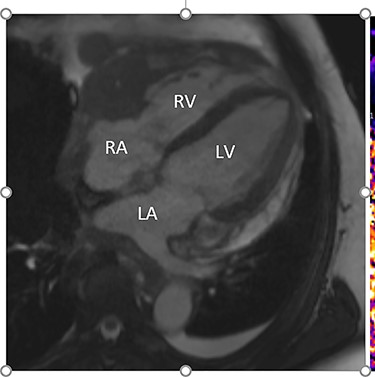

Intraoperatively, he developed new t-wave inversion on lead II of the 3-lead electrocardiogram (ECG). This resolved post-operatively, and he denied chest pain. He was kept in overnight for observation. The next morning, during the round, he reported central crushing chest pain the previous day that he had not disclosed. His ECG was repeated and demonstrated the t-wave inversion in lead II—indicating dynamic ECG changes. A troponin I level measured 27. As such, management for a non-ST elevation myocardial infarction was initiated and a cardiology consult organized, who advised continued acute coronary syndrome (ACS) treatment and an echocardiogram. This demonstrated a ‘pericardial mass (subcostal 3 cm × 2.5 cm) encroaching and extending outwards on both sides of the right atrioventricular groove’. ACS protocol was stopped and a cardiac magnetic resonance imaging (MRI) was organized (Figs 2 and 3).

Cardiac MRI (transverse plane) demonstrating an enhancing lesion surrounding the chambers of the heart.

This demonstrated a bulky mediastinal tissue (measuring 50% of the heart) that encased all the aorta and pulmonary artery as well as the coronary artery. It has malignant behaviour with multiple foci that breached fascial planes. It restricted the long axis of the heart but was not causing haemodynamic occlusion. It was non-resectable.